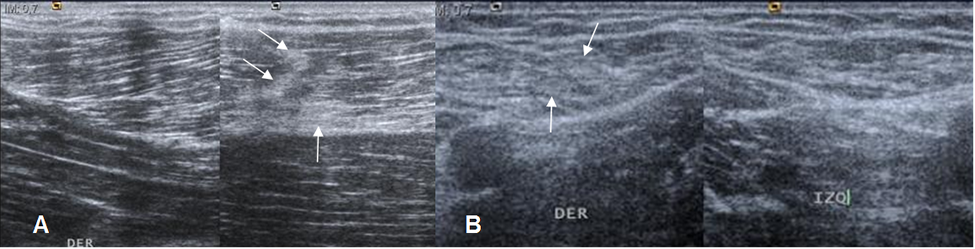

Fig 15 B. Distensión muscular grado 1.

A y B: Ecografías comparativas. Pérdida del patrón fibrilar normal, con áreas hiperecoicas (Flechas delgadas), que corresponden a lesión grado 1.